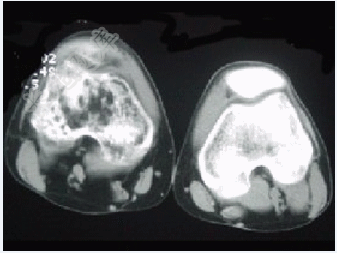

- 单项选择题患者女,28岁,右膝跌伤伴疼痛9年,加重及活动障碍1年半,经药物治疗及理疗后病情无好转,既往无特殊病史,查体跛行步态,触痛,请结合所提供的图像,选择最佳选项( )

A、骨巨细胞瘤

B、结核

C、骨肉瘤

D、滑膜肉瘤

E、软骨肉瘤